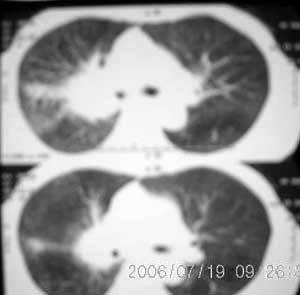

以下是引用jiangjing在2006-7-20 19:22:00的发言:[br]右侧肺门见有软组织肿块,边缘不规则,不光整,其周围肺内见炎性片状影,胸片示水平裂呈弧形上移,右上叶支气管狭窄,考虑右肺中央型肺癌伴阻塞性肺炎部分肺不张。

以下是引用1983在2006-7-20 21:53:00的发言:[br]右侧中央型肺癌伴阻塞性肺炎.

以下是引用卜一在2006-7-20 14:13:00的发言:[br]图象质量差了些,首先考虑:中心性肺癌伴阻塞性肺炎.因发生在右肺上叶尖后段,而且外带见二个空洞影,次考虑:不排除肺结核